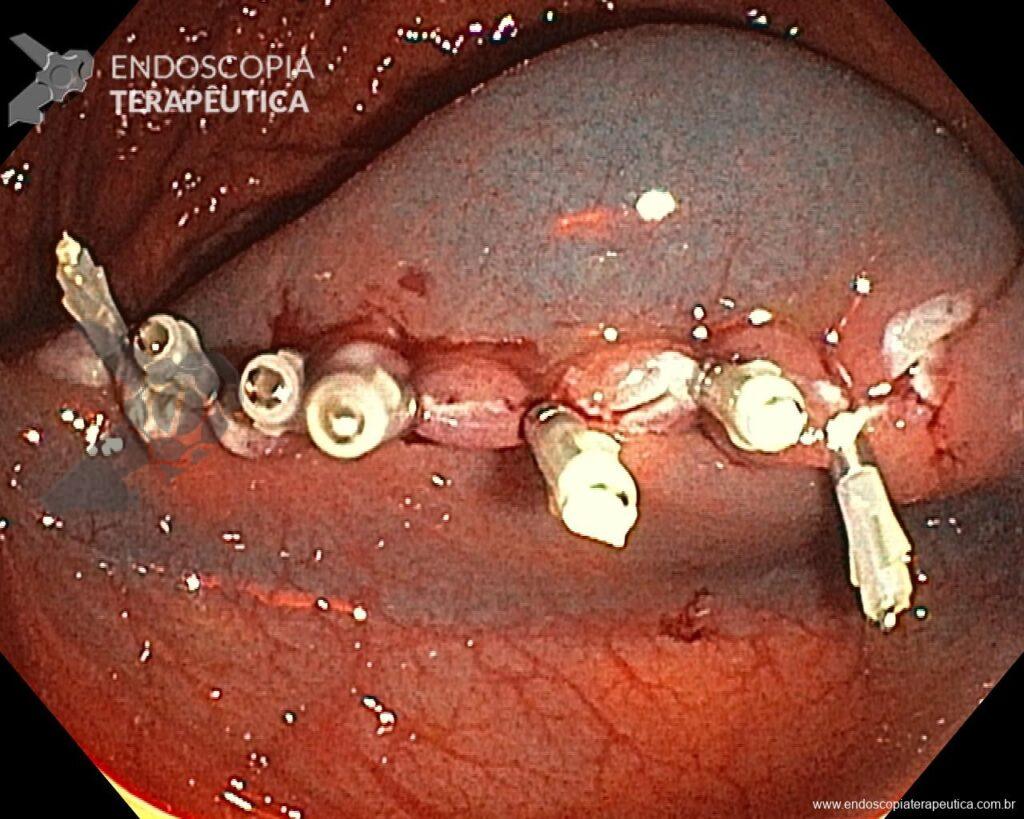

Una vez elegida la técnica de EPMR, tenga en mente que el objetivo debe ser la remoción completa de la lesión con la mayor seguridad posible. Para eso, la estrategia correcta es fundamental: no haga la burbuja submucosa toda de una vez, en vez de eso, haga inyecciones sucesivas seguidas del corte, preferentemente en el sentido proximal-distal; siempre que disponible, dé preferencia a soluciones viscosas, que garanticen una mayor patencia de la burbuja; utilice un asa más pequeña (10-15 mm) para sujetar la ampolla formulada; además de facilitar la operación, reduce el riesgo de perforación al intentar sujetar toda la lesión inadvertidamente.

5. No se preocupe por el sangrado

Si experimenta un sangrado intraoperatorio (SIP), no se preocupe, es solo sangrado. Si bien es cierto que solo la experiencia práctica le dará confianza con el SIP, prepárese para abordarlo sistemáticamente, como lo haría con cualquier otro procedimiento endoscópico. Antes de comenzar el procedimiento, asegúrese de que su sala de endoscopia esté completamente equipada y sea capaz de manejar todo tipo de SIP. Use todo lo que pueda sin preocuparse. Use la bomba de lavado para extraer la sangre del tejido objetivo y limpiar el punto donde necesita intervenir. Si considera que el vaso es pequeño (hasta aproximadamente 2 mm), puede coagularlo inmediatamente con la punta del asa en modo de “coagulación suave”. Por otro lado, si el vaso es mayor de 2 mm, usar unas pinzas de coagulación es una estrategia más efectiva. Mientras espera el accesorio, si usa un tapón en la punta del dispositivo, úselo como un dedo y aplique presión sobre el vaso. Una vez que tenga listo el dispositivo, utilice de nuevo la bomba de agua para limpiar la zona, abra la pinza y sujete el vaso, tirando de él hacia usted (y alejándolo de la pared) antes de la coagulación. Se debe minimizar el uso de coagulación con plasma de argón (APC) durante la REM, al igual que los clips hemostáticos, que deben utilizarse cuando, tras haberlo intentado todo, el sangrado persiste.

En vista de lo anterior, para el caso ejemplificado anteriormente, se optó por la resección mediante la técnica EPMR, tanto por el tipo morfológico (LST-G-H) y las características superficiales de la lesión (JNET 2A), como por su ubicación (ciego), que presenta un mayor riesgo de complicaciones.